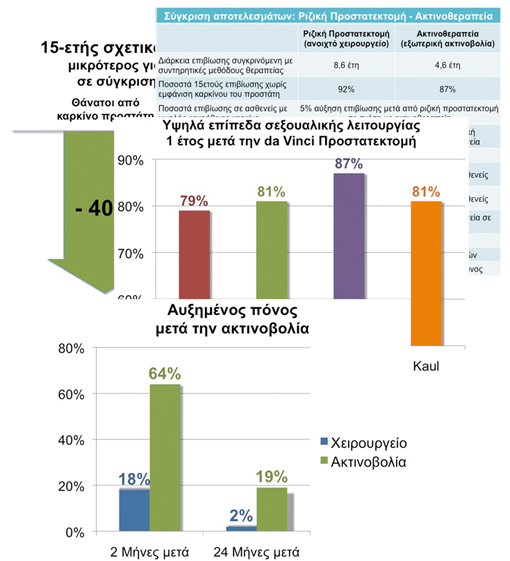

Μία μελέτη σε 3.159 ασθενείς έδειξε ότι 15 χρόνια μετά την θεραπεία, εκείνοι οι ασθενείς που υποβλήθηκαν σε ριζική προστατεκτομή είχαν 40% χαμηλότερο κίνδυνο θανάτου από καρκίνο του προστάτη σε σύγκριση με τους ασθενείς που αντιμετωπίστηκαν με ακτινοβολία.1

Σε μία μελέτη με 844 ασθενείς με εντοπισμένο καρκίνο του προστάτη, οι ασθενείς που υποβλήθηκαν σε προστατεκτομή είχαν υψηλότερα ποσοστά επιβίωσης από καρκίνο του προστάτη σε σύγκριση με τους άνδρες που επέλεξαν άλλες μορφές θεραπείας.2

Ποσοστά επανόδου της στύσης 1 έτος μετά την da Vinci Προστατεκτομή. Τα ονόματα παραπέμπουν στους συγγραφείς των μελετών.

Διάφορες μελέτες έδειξαν ότι ασθενείς που ήταν προεγχειρητικά σεξουαλικά ικανοί παρουσιάζουν υψηλότερα επίπεδα ανάρρωσης της σεξουαλικής λειτουργίας (οριζόμενη σαν στύση ικανή για κολπική διείσδυση) μέσα σ’ ένα χρόνο μετά την da Vinci Ριζική Προστατεκτομή. Εφαρμόζοντας ένα μετεγχειρητικό πρόγραμμα ανάρρωσης της σεξουαλικής λειτουργίας με φάρμακα και ειδικές ασκήσεις μπορεί να επιταχυνθεί η επάνοδος της αυτόματης στύσης.

Ασθενείς μετά από ριζική προστατεκτομή αναφέρουν λιγότερους πόνους κατά την ούρηση σε σύγκριση με ασθενείς μετά από ακτινοθεραπεία (βραχυθεραπεία).

Οι παρακάτω πίνακες συγκρίνουν τ’ αποτελέσματα θεραπειών καρκίνου του προστάτη και ειδικότερα αντιπαραθέτοντας το χειρουργείο (ριζική προστατεκτομή), που θεωρείται ο χρυσός κανόνας για την θεραπεία του εντοπισμένου καρκίνου του προστάτη, με την ακτινοθεραπεία (θεωρούμενη σαν βραχυθεραπεία και σαν εξωτερική ακτινοβολία). Τα δεδομένα αφορούν την επιβίωση, την υποτροπή του καρκίνου, την συχνότητα εμφάνισης καρκίνου του ορθού και της ουροδόχου κύστης, την λειτουργία του εντέρου, την λειτουργία της ουροδόχου κύστης και της στύσης.

Σ’ αυτόν το πίνακα η ριζική προστατεκτομή περιλαμβάνει όλα τα είδη των ριζικών επεμβάσεων στον προστάτη (ανοιχτό χειρουργείο μέσω μίας μεγάλης τομής στην κοιλιά, συμβατική λαπαροσκοπική ριζική προστατεκτομή καθώς και da Vinci προστατεκτομή). Όπως μπορείτε να διαπιστώσετε το χειρουργείο προσφέρει μετρήσιμα σημαντικά περισσότερα προτερήματα συγκριτικά με την ακτινοβολία όσον αφορά την τα αποτελέσματα και την επιβίωση.

Results: After adjusting for age, race, tumor grade, comorbid disease, income status, and year of diagnosis, the overall survival rate at 15 years was 35% for conservative management, 50% for radiotherapy, and 65% for radical prostatectomy. The corresponding prostate cancer-specific survival rates were 79%, 87%, and 92%. Patients undergoing radiotherapy or radical prostatectomy had lower overall mortality than patients undergoing conservative management (adjusted relative risk 0.67 for radiotherapy and 0.41 for prostatectomy; P <0.001). The increase in the survival duration was 4.6 years with radiotherapy and 8.6 years with radical prostatectomy.